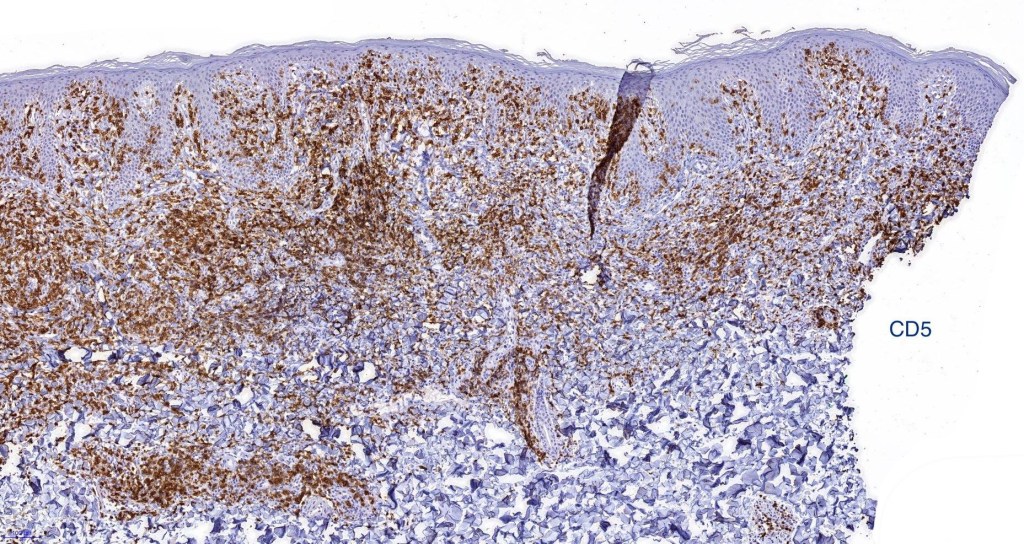

Immunohistochemistry

•TCRβ, CD45RO, IL-2R, CLA, CD25, CD2, CD3, CD4, CD5, CD7 +ve

•Variable loss of CD5 (supports the diagnosis) & CD7 (not so helpful as also seen in inflammatory dermatoses)